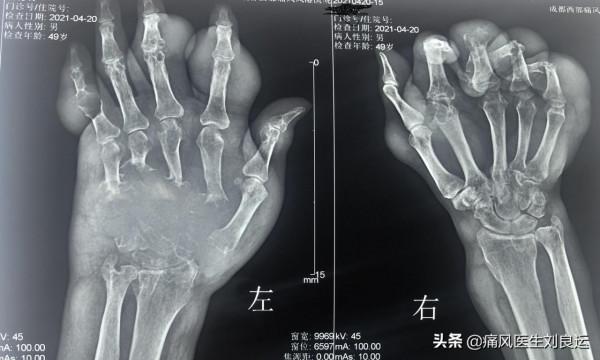

在我的診室,牟先生告訴我:“劉醫生,您看,我左手手指是彎的,打不直。”他舉起他的雙手,放在我的桌子上。

牟先生並不知道自己手指上“白色疙瘩”是什麼,我告訴他:“您這是痛風石呢!怎麼能自己挑呢?您看您的手指都已經破了,破潰的地方這些白色的像粉筆灰的就是尿酸鹽結晶。”

痛風石內的主要成分是尿酸鹽結晶,當痛風破潰後,這些尿酸鹽結晶會由破裂的面板開口流出;尿酸鹽結晶為乳白色,呈半固體狀,久置後則變成石灰粉狀固體。

很多人以為痛風石是因為痛風時間長了才決定的,但實際上痛風石是因為尿酸濃度持續過高造成的。比如有些痛風性關節炎患者,尿酸在600μmol/L以上,人體排洩來不及,那麼就會沉積在軟骨、滑液膜及軟組織中,形成尿酸鹽結晶的堆積;而且尿酸持續居高不下,就會越堆積越多,就容易形成痛風石。

痛風石與慢性痛風性關節炎的形成,都是慢性過程。尿酸鹽結晶不僅會堆積在關節形成痛風石,堆積多了也會影響血管與腎臟,甚至造成嚴重腎功能衰竭,而腎病加重則會進一步影響尿酸排洩,從此形成了惡性迴圈,導致痛風石在體內的沉積進一步增加。